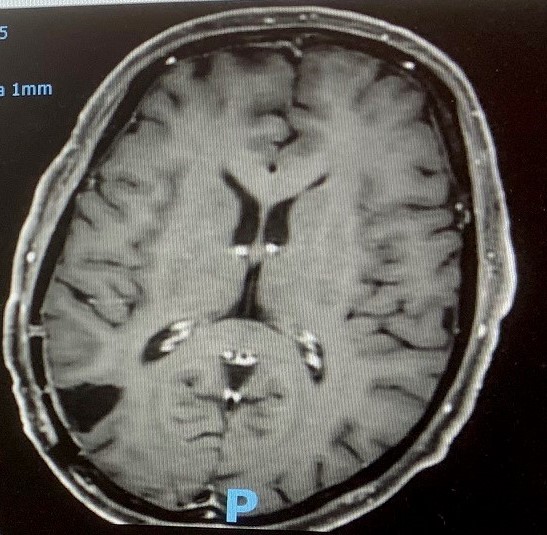

The results from the MR-scan were very positive. There are no signs of tumour activity in or around the operation site. Similarly, there are no signs of tumour activity anywhere else within my brain. Just for interest, I have included two images from the MR-scan. The left-hand image was recorded in September and shows the tumour as a fuzzy white disc in the bottom left section of the picture. The same area in the right-hand image shows that the hole left after the operation is filled with cerebral fluid. No fuzzy white discs can be seen, so for the time being things are looking good.